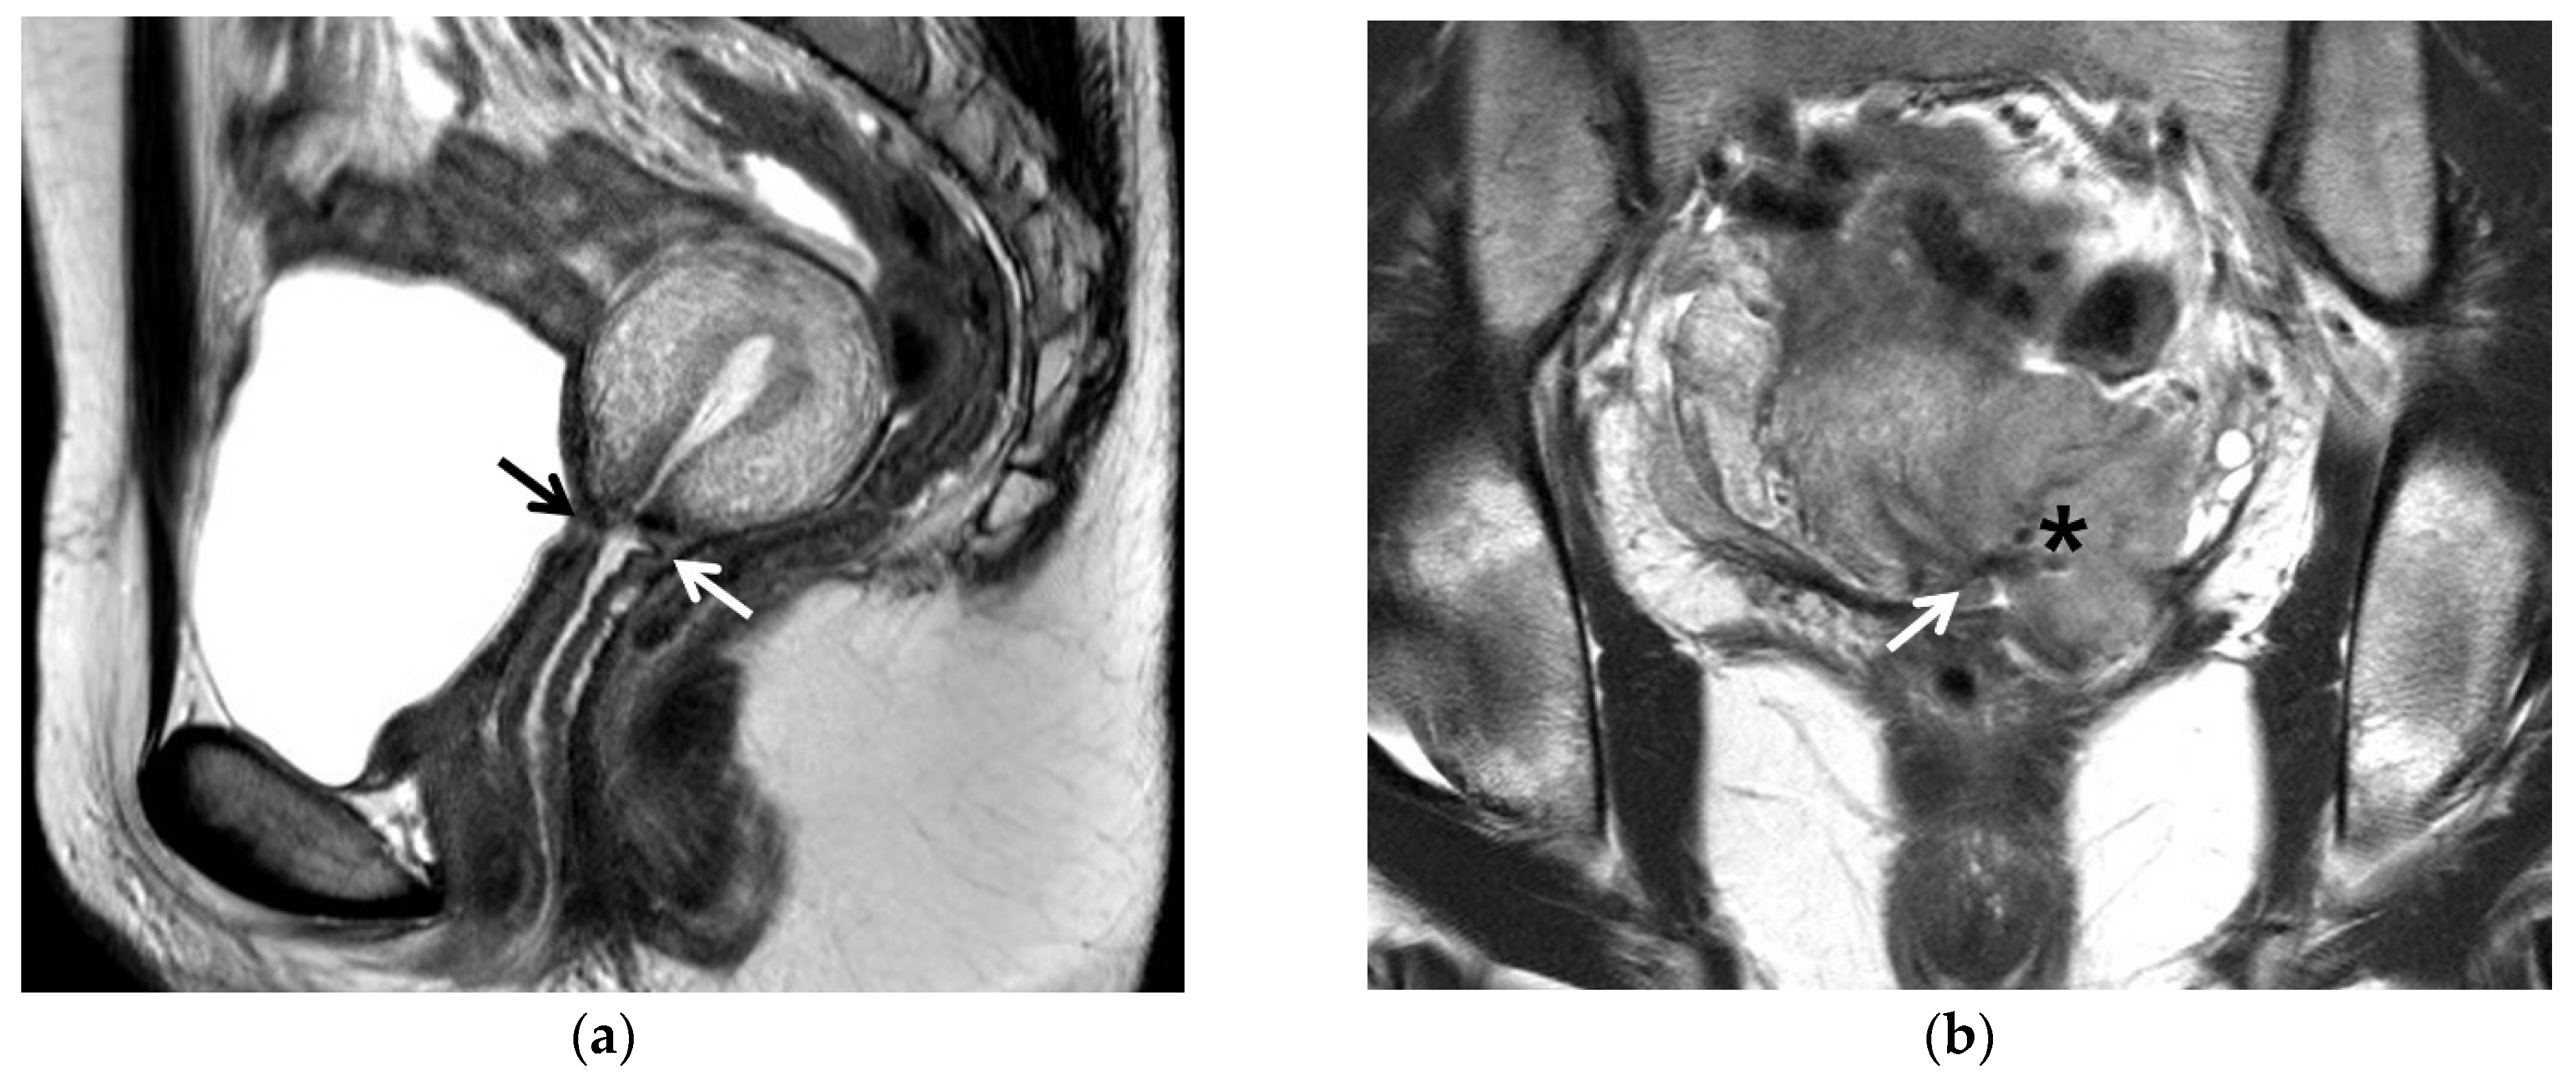

4. Post-Conization MRI

7. Early Detection of Recurrent Cancer